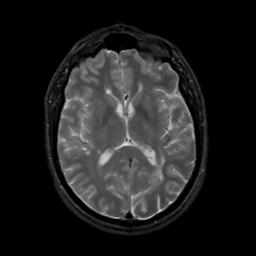

MR Study #6, March 17, 1991 -- Slice #27

[Home][Help][Clinical][Tour 1][Tour 2] Slice 27